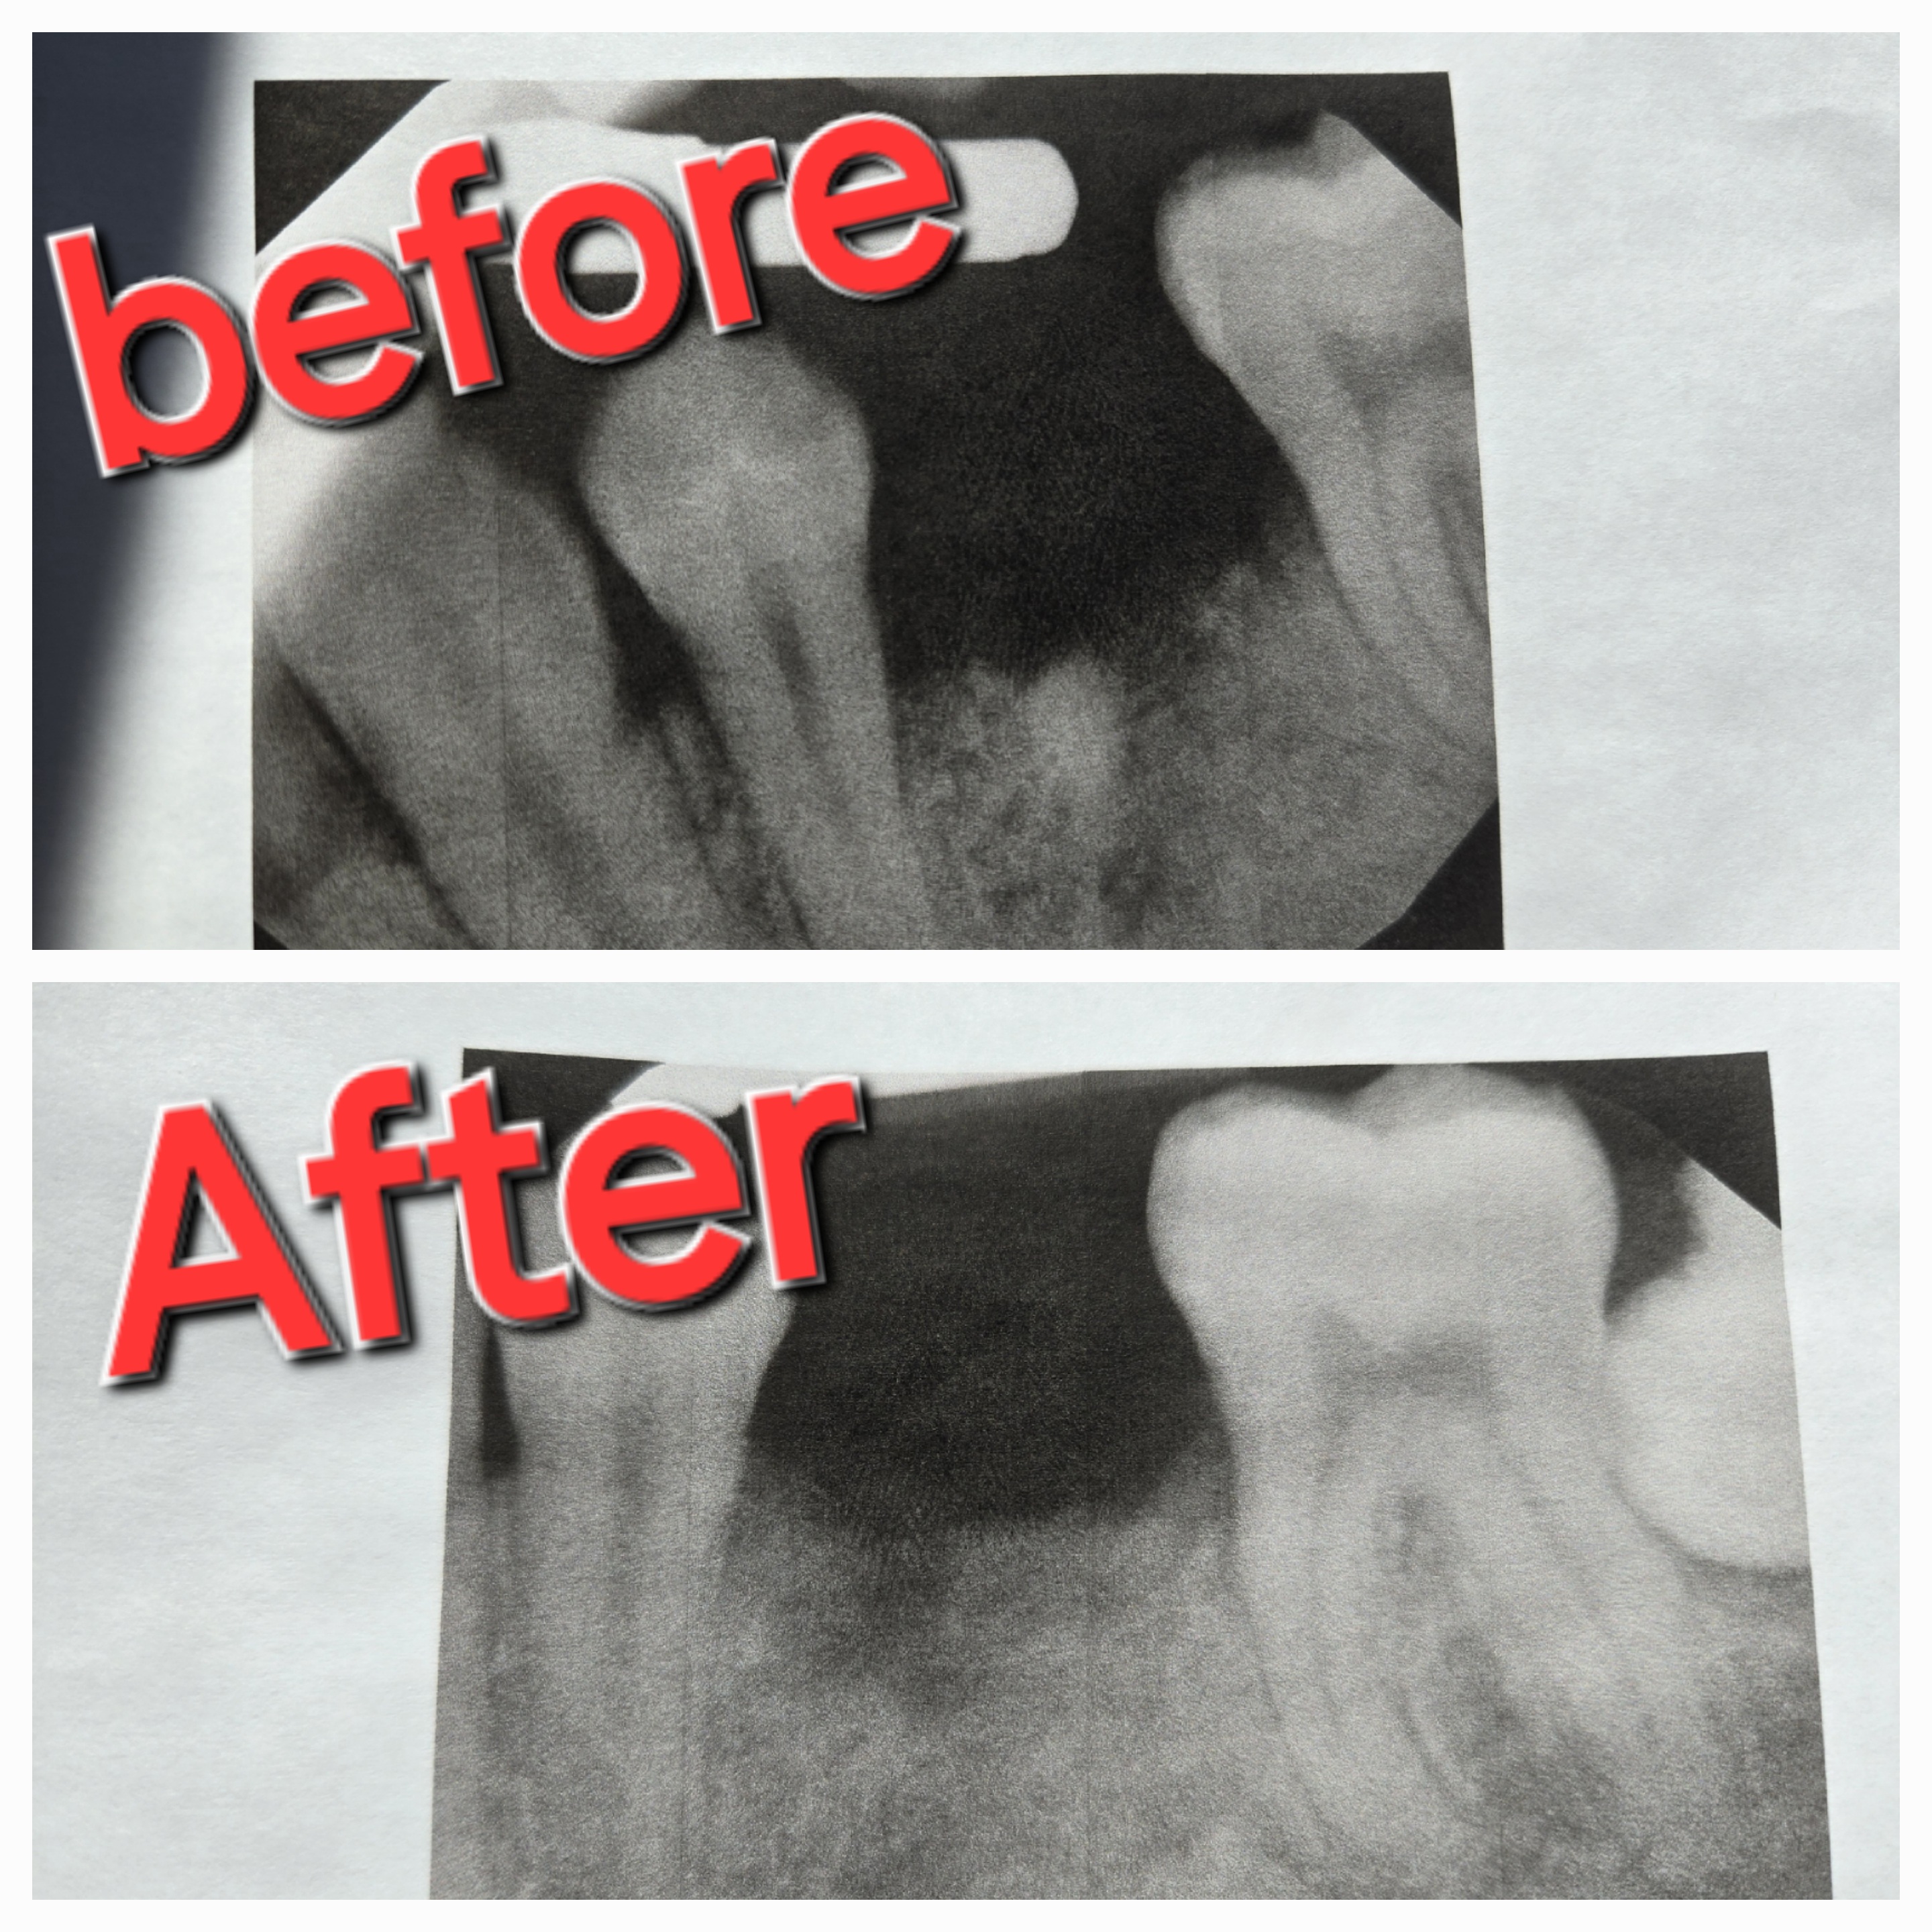

i had a toothache called they said to come the next day i went and then they said i didnt have a appointment then had to go back but had to wait 3 days i went back they pulled the tooth and it just kept hurting called american family dentistry said theres nothing they could do and it just kept hurting after 4 weeks of it hurting went to a different dentist they x rayed it and found that they were a lot of tooth still left that was not taken out i have proof of this a before xray when the other dentist office x rayed it and w... read more